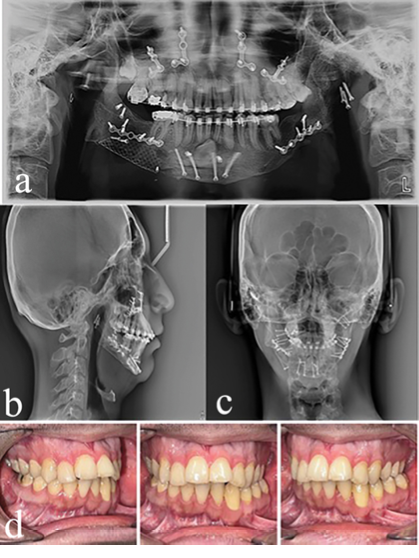

In the upper arch, orthodontic treatment plan was non-extraction due to the proper torque of the anterior upper teeth and the discrepancy not being reduced compared to the lower jaw. We expanded the upper arch and corrected the crossbite of the lateral incisors. Orthognathic surgery was performed after fixed orthodontic treatment (Figures 5 and 6).

As shown on radiographic images, the lower right canine tooth is impacted. Due to its horizontal position, it cannot be returned to its normal position due to the risks and injuries during surgery. The canine tooth remained in that position. Considering the severity of mandibular crowding, the mandibular right lower incisor was removed. During the fixed orthodontic treatment of the lower jaw, to prevent the resorption of the roots of the anterior teeth, they were not engaged, and arch coordination was performed. Finally, bimaxillary surgery was performed for the patient at 22 years of age. At the end of the treatment, the maximum mouth opening was 13 mm and overjet and overbite were 3 mm. Table-1 presents the results of cephalometric analyses. Figure 6 shows the results of the treatment. Figure 7 is a comparison between the periods before and after treatment. Figure 8 shows the superimposition of the patient at 7, 15, and 22 years of age based on cranial base adaptation. The patient was referred for the replacement of mandibular second molar with implants.

Figure 6. Panoramic views and lateral cephalometry, PA cephalometry, and intraoral images at the end of treatment.